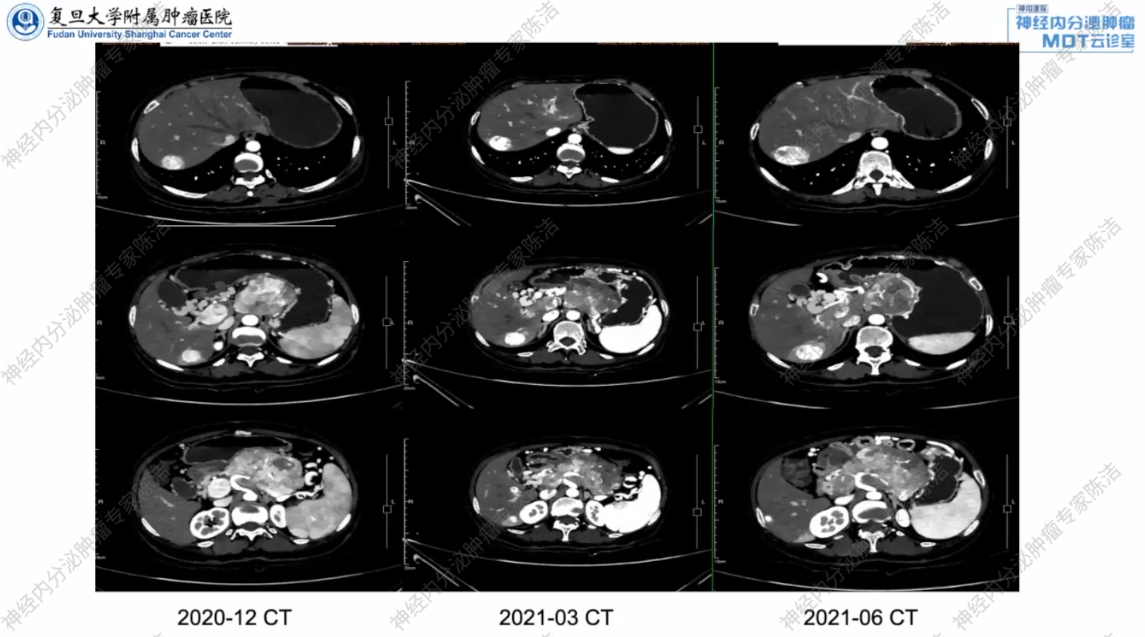

治疗方案:考虑到肿瘤富血供的特点,2020年12月治疗方案调整为抗血管生成靶向药物索坦37.5mg每日一次。但患者因不耐受,1个月后减量至25mg每日一次。

2021年3月,复查增强CT显示,胰腺体尾部巨大肿块,较前略变小,并局部外侵,周围淋巴结转移,肝转移同前相仿,门静脉主干及SMV癌栓形成,继续索坦25mg每日一次治疗。2021年6月复查增强CT显示,胰尾肿块增大,局部外侵,周围淋巴结转移,肝转移较前增大,门静脉主干及SMV癌栓形成,更换为CAPTEM方案(卡培他滨+替莫唑胺)化疗。

2021年8月,患者转至复旦大学附属肿瘤医院继续治疗。复查增强CT显示,胰体尾肿块,考虑MT,脾血管受累,门脉癌栓形成,SMV可疑受侵,肝多发转移,门脉海绵样变性。与外院2021年6月CT相比,疗效评估为部分缓解(PR)。

2021年11月,再次复查增强CT,病灶持续缩小,疗效评价仍为PR。

2022年3月,复查增强CT显示胰腺体尾部及肝转移病灶大小与前次相仿,部分病灶略有缩小,疗效评估为缩小的疾病稳定(SD)。

放射诊断科汤伟教授:本病例的系列CT影像动态、直观地记录了不同治疗方案下的疗效变化:索坦治疗初期稳定,后快速进展;而在换用CAPTEM化疗后,无论是胰腺原发灶还是肝转移灶,都带来了持续的肿瘤退缩。这一系列的影像变化为临床判断疗效、调整方案以及最终评估手术可能性提供了至关重要的客观依据。